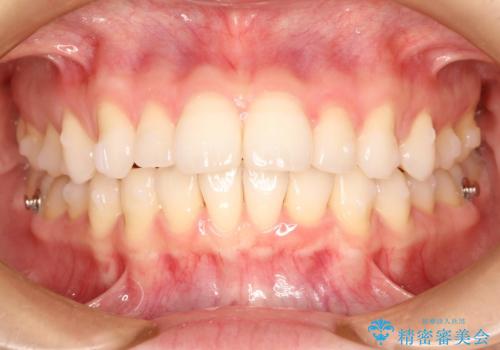

インビザラインで出っ歯を改善する 抜歯をしないinvisalign治療

- 1年5ヶ月

- 非抜歯・遠心移動による前突の改善をマウスピースにて計画した。

非抜歯矯正の場合、大きく前歯を下げることはできませんが、奥歯の遠心移動や歯のサイズダウンにより歯軸を立て、見かけ上の出っ歯感をある程度改善することができます。